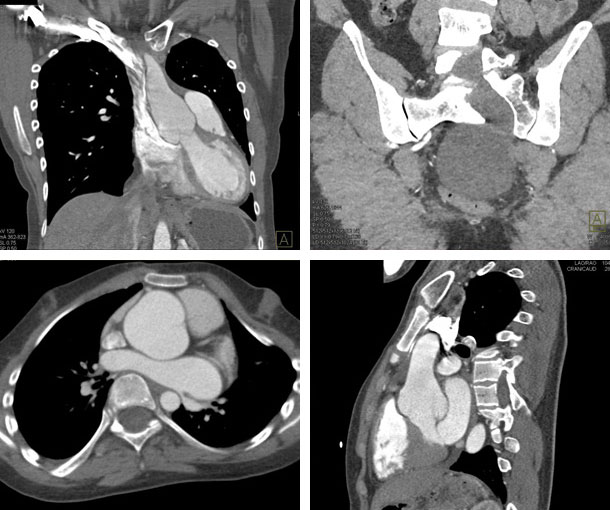

Marfan Syndrome CT Findings

- Dilation of the aortic root

- Dissection of the aorta (usually thoracic aorta)

- Aortic aneurysm

- Dilation of the main pulmonary artery